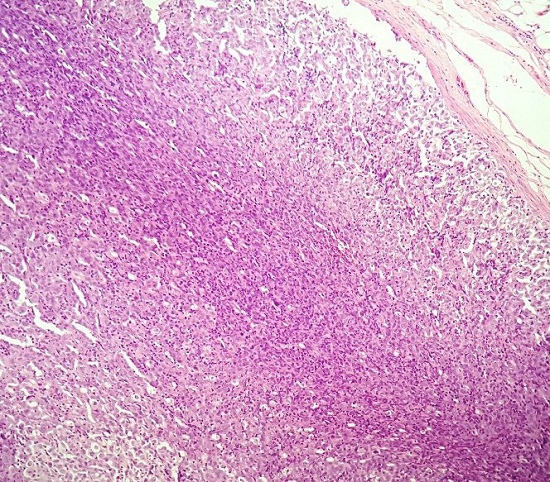

On histology, the lymph node showed complete effacement of its architecture by diffuse proliferation of large-sized pleomorphic neoplastic cells (Figure 1).

These cells had large, multilobated nuclei, coarse vesicular nuclear chromatin, and prominent nucleoli with abundant amount of eosinophilic cytoplasm. Large multinucleated cells were also noted (Figure 2A and Figure 2B). Numerous lymphocytes and few neutrophils interspersed these tumor cells. Frequent atypical mitotic figures were also noted.